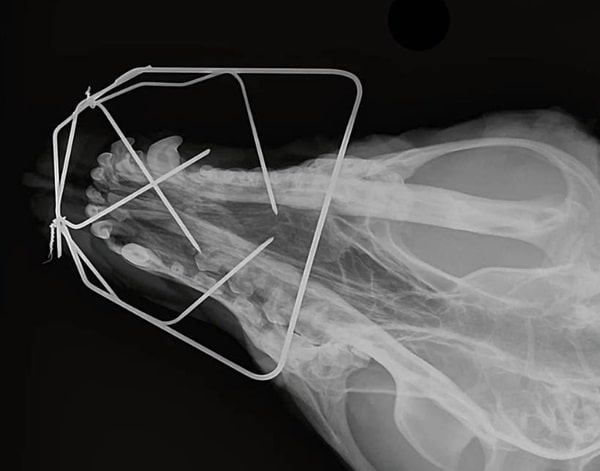

Як правило, накісткові пластини використовують для стабілізації переломів каудальніше кута НЧ. За більш ростральних ушкоджень зазвичай застосовується ортодонтична стабілізація композитними матеріалами з боку ротової порожнини. Альтернативним методом є стабілізація зовнішнім фіксатором. Ці методики не потребують втручання безпосередньо в ділянку перелому, менше порушують кровопостачання в цій ділянці, що часто має вирішальне значення.

Пальця

Переломи пальців можливі, але вкрай рідко це входить у сферу інтересу хірурга. Такі пошкодження мало впливають на опороздатність. З цієї причини вони нечасто є причиною звернення в клініку.

Ще рідше можуть бути прийняті рішення щодо відновлювально-реконструктивної хірургії.

Зазвичай подібні травми підлягають самостійному загоєнню, на відміну від ушкоджень на сегмент вище. Переломи п’яти або плесна зазвичай вимагають хірургічної стабілізації. У цих випадках використовують комбінацію інтрамедулярної і зовнішньої стабілізації, оскільки інші методи фіксації в цій ділянці зазвичай малозастосовні.